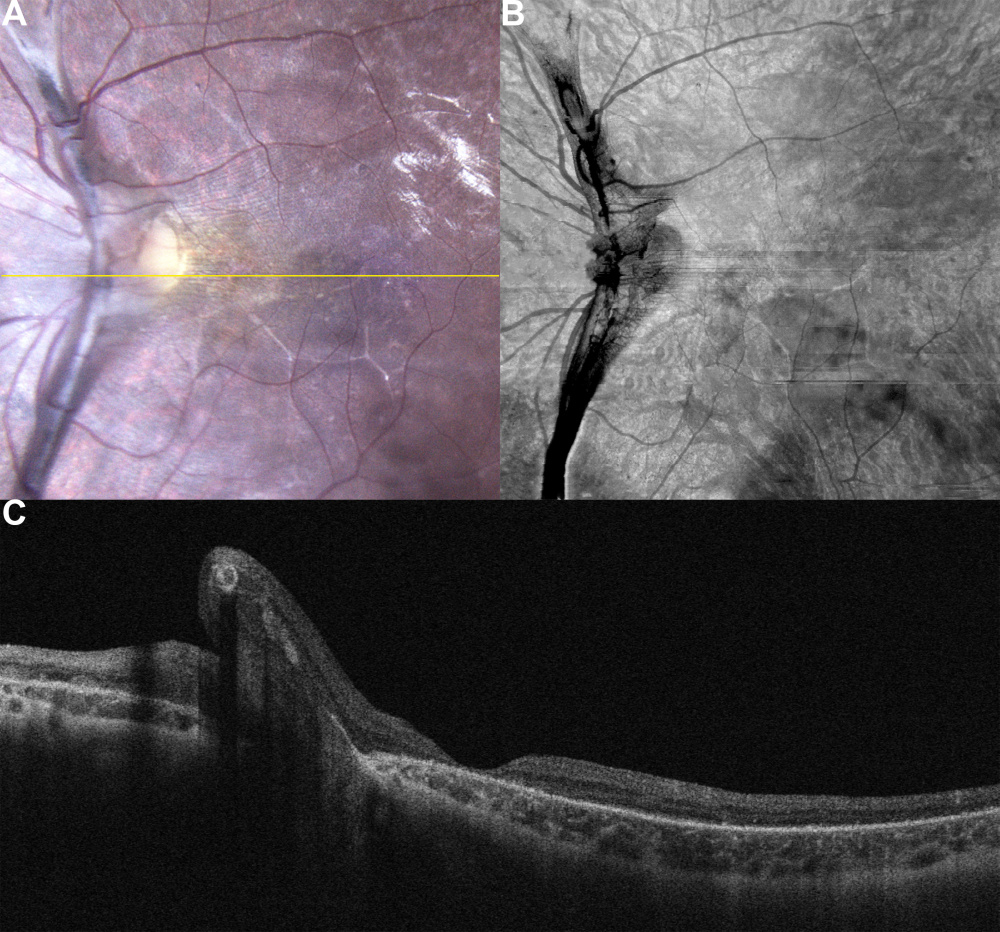

Título: Retinal Incarceration At The Optic Nerve Head

Autor: João Domingues Vaz

Coautores: Diogo Gonçalo Reis Cabral

Instituição: ULSAS, Hospital Garcia de Orta, Almada

Descrição: Adolescent with long-standing visual impairment of left eye showed retinal changes consistent with old ocular trauma.